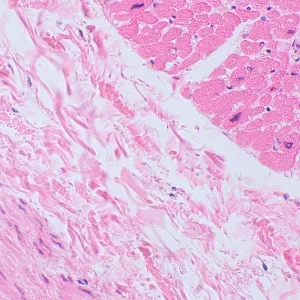

С помощью микроскопа MAGUS Bio 250TL изучают тонкие срезы и мазки биологических образцов. Исследования ведутся в светлом поле в проходящем свете. В качестве осветителя выступает 3-ваттный светодиод, а оптика включает планахроматические объективы, рассчитанные на бесконечность. Микроскоп поддерживает установку дополнительных аксессуаров, в том числе устройств для работы по методам темного поля, поляризованного света и фазового контраста. Этот микроскоп – идеальный выбор для лабораторной диагностики, научных исследований и обучения.